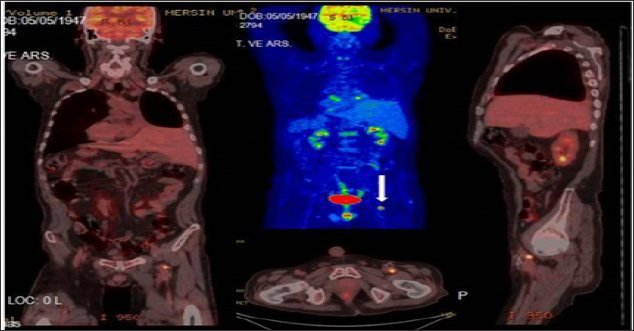

Figure 2: Left main femoral artery (white arrow) biopsy proven focal TT (SUVmax:9.27) in a lung cancer 68 year old male patient.

FDG-PET/CT imaging performed for staging, restaging and treatment response in oncological patients and patients with suspected malignancy. A total of 37 patients with tumor thrombus and benign thrombus were included. Patients who had confirmed primary malignancies ( lung cancer in 7 patients, gastrointestinal and hepatobiliary malignancies in 13 patients, genitourinary malignancies in 8 patient, sarcoma in 2 patients, lymphoma in 1 patient, laringeal cancer in 2 patients or suspected malignancies in 4 patients) were undergone PET-CT imaging. The most common malignancy was lung cancer (Table 1). PET-CT imaging findings of a total of 37 patients with suspected tumor thrombus (25 men, 12 women, mean age: 53.62-range: 8-82) were evaluated retrospectively. Of the 37 patients 56 thrombus regions (45 benign and 11 malignant thrombus) were shown by PET-CT. A total of 8 (21.6 %) patients (7 M, 1 FM) with mean age 47.75 (Age Range: 8-69) were included in malignant thrombus group (Group I). A total of 29 (78.4 %) patients (14 M, 7 FM) were included in benign thrombus group (Group II). Two patients had more than one vessel, one of which had 3 and the other had 2 malign thrombus regions in group I. FDG uptake pattern was linear in 9 of the 11 segments and focal in 2 segments. (Figures 1-3) illustrates three demonstrative tumour thrombus patients' PET-CT images. Tumor thrombus in 11 segments in 8 patients and benign thrombus in 45 regions in the other 29 patients were reported in the evaluation of a total of 56 thrombi region in 37 patients on visual analysis and according to the increased metabolic activity. Various vessels were affected. The most common region of thrombosis was defined as vena cava inferior. SUVmax values ranged from 7.91 to 20 (mean:12.8) in 8 tumor thrombus patients. Compared to mediastinal region increased metabolic activity was not detected in none of the 29 patients with benign thrombus and these patients were treated with anticoagulant agents.